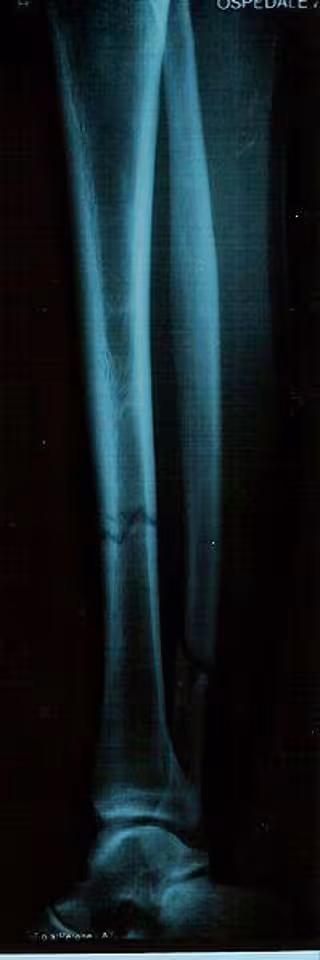

fractura, tibia

La osteoporosis es una enfermedad de la baja masa ósea causada por una pérdida excesiva y la pobre formación de los huesos. La serotonina se conoce mejor por su papel como un neurotransmisor del cerebro, pero esta molécula es también producida por los intestinos e inhibe la formación ósea.